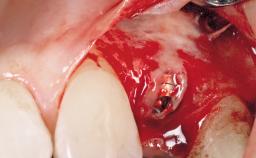

Mauricio Araujo and Flauvia Matarazzo present this straightforward clinical case, demonstrating the potential effect of implant placement depth on the resolution of peri-implant treatment. A 42-year-old systemically healthy female patient, a non-smoker with no history of periodontitis, was treated at the Dental Clinic at the State University of Maringá, Brazil between 2008 and 2009, when she received five implants restored with single crowns at sites 14, 26, 27, 36, and 46. After delivery of the implant-supported prosthetic restorations, the patient was enrolled in the supportive peri-implant therapy (SPiT) maintenance program at the same university.